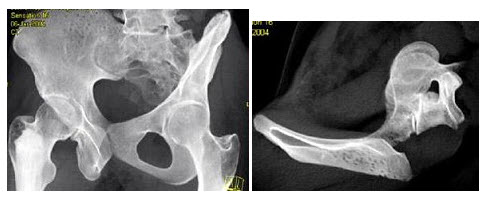

A.5%

男,31岁,感左坐骨区胀痛,无发热,结合所提供的图像,最可能的诊断是()

A.骨巨细胞瘤

B.骨囊肿

C.纤维异常增殖症

D.动脉瘤样骨囊肿

E.非骨化性纤维瘤